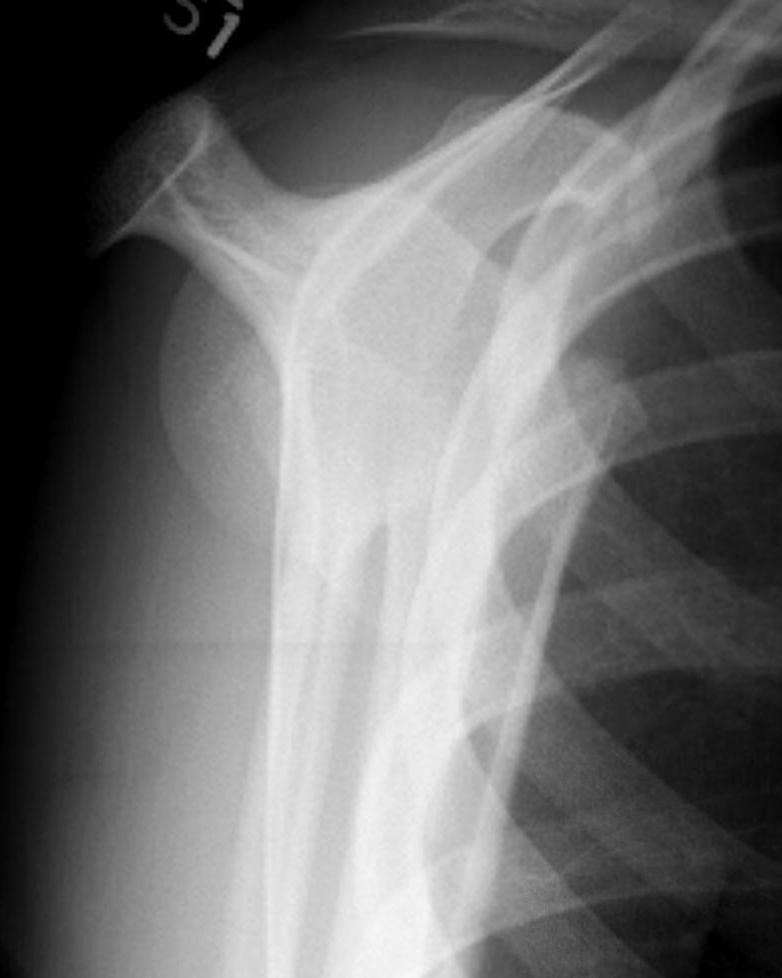

Case: 16 year old boy

Initial injury 18 months post injury